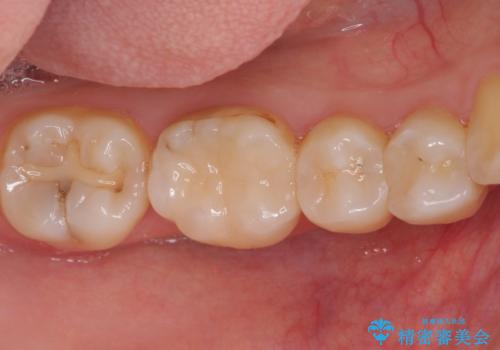

- 下の奥歯(右下7・左下7)にあって目立ってしまう銀歯を白くしたいとのことで来院された患者様です。

セラミックインレーにて修復治療を行うこととしました。

セラミックインレーを装着したことで、とても自然な仕上がりとなりました。